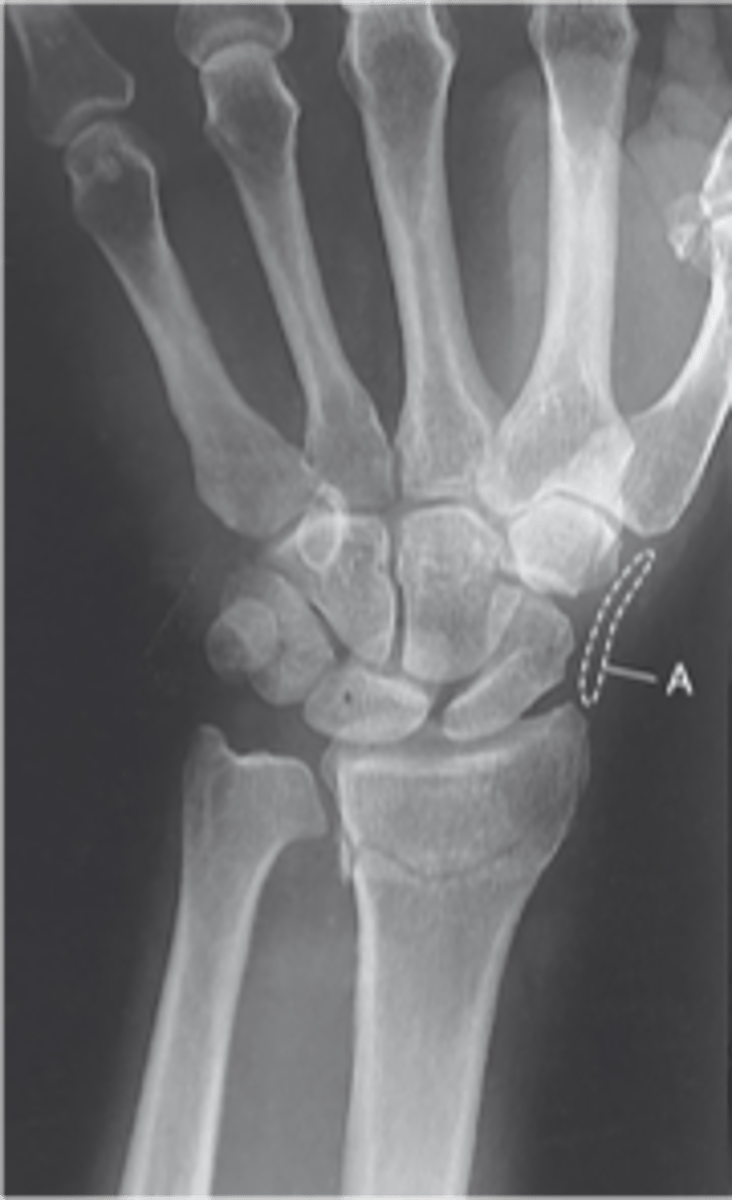

PA Wrist

PA Oblique Wrist

scaphoid fat pad

pronator fat stripe